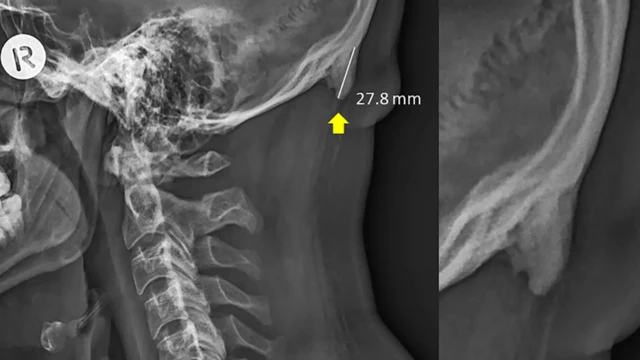

El abultamiento en punta, llamado también "protuberancia occipital externa", se encuentra en la parte posterior del cráneo, justo arriba del cuello.

Fuente de la imagen, David Shahar et al

Si tienes uno es probable que puedas sentirlo con tus dedos y si no tienes pelo puede ser visible.

Hasta hace poco se pensaba que esta protuberancia era muy poco común.

Junto a un colega analizó más de mil radiografías de cráneos de personas entre 18 y 86 años, y registró los problemas de postura de cada una de esas personas.

Lo que los científicos descubrieron fue sorprendente.

El abultamiento era mucho más común en el grupo entre 18 y 30 años.

Una de las mayores sorpresas para Shahar fue cuan grandes eran las protuberancias. Los abultamientos mayores median unos 30 mm.